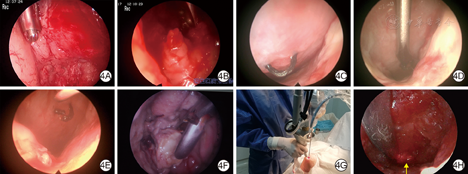

内镜下创面处理的概要如下:按慢性创面修复原则进行,对窦道(腔)的所有分支进行合理、有效的清创[8]。清创时既要充分到位,又要避免清创过度,影响创面生长闭合[9]。对暴露的骨质和骨膜,如已有明显骨感染或骨坏死征象则用咬骨钳咬除或磨钻磨除。使用磨钻时,对骨皮质可从3 000 r/min高转速起步进行磨削以提高处理效率,过程中使用生理盐水持续冲洗冷却;对骨松质可用较低转速逐步磨削。骨质清创后的渗血须用骨蜡或纤维素等行止血处理。部分慢性窦道(腔)创面内有明显的纤维组织增生,阻碍创面愈合[10]。对于较小的团块状的纤维组织,根据具体生长部位和方向,可使用左弯或右弯篮钳咬除;对于较大的呈板层状覆盖创面的纤维组织,须先使用钩刀切开纤维板暴露断层,再使用刨削刀头从切开断层处进行卷吸刨削;对于部位较深或质地硬韧刨削效果不佳的纤维组织,可使用二氧化碳激光对其进行面状清理。慢性窦道(腔)创面腔内常有异物或坏死组织,其中较为疏松者可根据窦道(腔)尺寸及被清理对象的大小,选取合适规格的息肉钳摘除或咬除;对其中较为致密者可使用刨削刀头或磨钻清除。外科缝线等则可使用内镜专用剪刀剪断清理。见图4。清创完成后可镜下灌注敷用抗感染或清除生物膜药物,减轻局部炎症反应和细菌负担等;或使用促创面生长药物,如生长因子等。